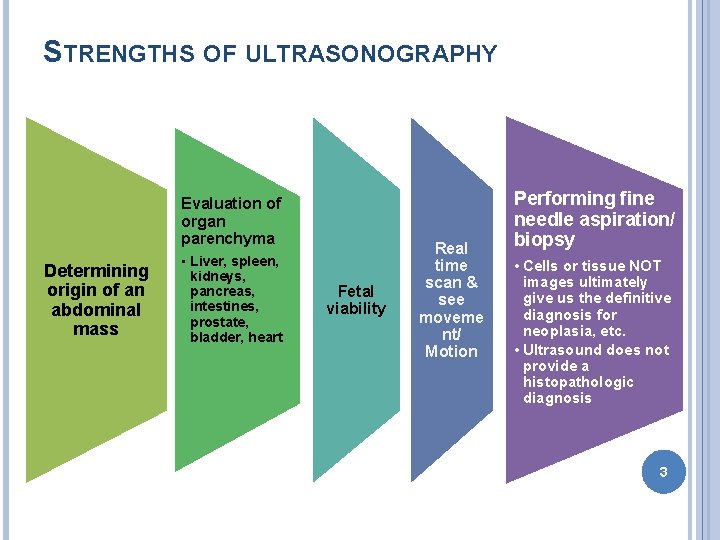

STRENGTHS OF ULTRASONOGRAPHY Evaluation of organ parenchyma Determining origin of an abdominal mass • Liver, spleen, kidneys, pancreas, intestines, prostate, bladder, heart Fetal viability Real time scan & see moveme nt/ Motion Performing fine needle aspiration/ biopsy • Cells or tissue NOT images ultimately give us the definitive diagnosis for neoplasia, etc. • Ultrasound does not provide a histopathologic diagnosis 3